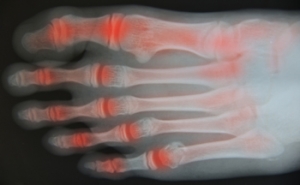

The feet and ankles contain numerous joints that can be affected by several types of arthritis. Osteoarthritis, which has been called “wear and tear” on the joints, can develop slowly and worsen over time. It is caused by the deterioration of the cartilage that sits between the bones and can cause stiffness, pain, loss of flexibility, bone spurs and swelling. Inflammatory arthritis, of which there are several varieties, causes pain, swelling, redness, and/or heat around the joint. The most common form of arthritis is rheumatoid arthritis which is an autoimmune condition that attacks healthy cells and can cause long-term damage to the foot and ankle joints. Psoriatic arthritis is an overreaction of the immune system and can contribute to plantar fasciitis and Achilles tendinopathy, both extremely painful conditions. Another type of arthritis, one that usually attacks the big toe, is commonly called gout. It is caused by crystals that form inside the joint, producing extreme pain, swelling and redness. If left untreated it could lead to osteoarthritis. If you are experiencing any of these symptoms, it is a good idea to consult a podiatrist for a full diagnosis and options for treatment.